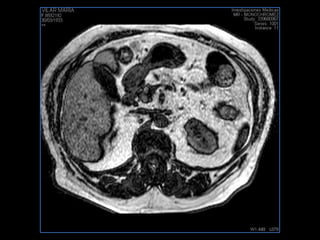

PROTOCOLO abdomen COR T2, AXIAL supresion grasa AX T1 +SAG T2  CON   GADOLINIO :  COR T1+AX T1(DIN) SAT: NO  FASE: RL THK: 6MM  COIL:  GAP: (FACTOR 1.4) 2MM FOV: 40 CM NEX:2 SINCRONIZACION RESPIRATORIA EN 3 O 4 CICLOS ALE

resonancia de abdomen